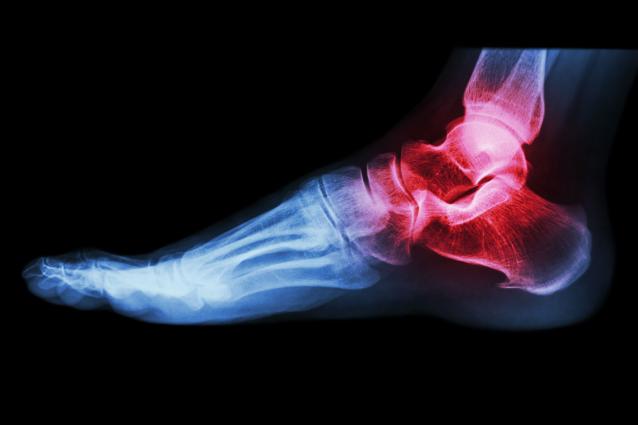

Une arthroscopie de cheville est une procédure chirurgicale durant laquelle une petite caméra (arthroscope) de trois millimètres de diamètre est introduite dans l’articulation de la cheville pour permettre au chirurgien de voir et de traiter différentes pathologies à l'intérieur de la cheville. De nombreuses maladies des ligaments, du cartilage et des os de la cheville peuvent ainsi être traitées par arthroscopie.

Une blessure à la cheville qui ne parvient pas à guérir avec les traitements et dans les délais habituels ou des maladies articulaires telles que l'arthrose et les conflits de cheville peuvent être prises en charge de cette manière. Voici d’autres exemples de pathologies où l’arthroscopie fait actuellement office de référence en matière de traitement :